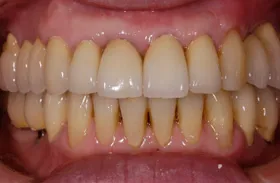

■治療前:上下顎 義歯での食事に満足されていない

■治療後:上下顎 複数本のインプラントを使い固定式で治療

| 主訴 | 現在義歯を使用しているが、しっかりと咬んでなんでもおいしく食事したい |

| 治療方法 | 上下顎 複数本のインプラントを使用しての治療 |

| 治療期間 | 約1年 |

| 通院回数等 | 約20回 |

| 費用 | 約600万円(税込) |

| リスク・副作用 | 術後の腫れ・痛み |